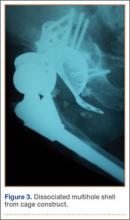

Thirteen patients with major osseous deficiencies of the pelvis were treated using this technique. At mean follow-up of 64.2 months (range, 3-133 months), 10 of the 13 patients had favorable outcomes without further surgery. One patient developed recurrent aseptic loosening that required re-revision, another patient developed recurrent instability that required acetabular liner and femoral head exchange, and a third patient with poor balance fell multiple times. This patient’s ninth fall resulted in dissociation of the acetabular shell from the cage (Figure 3), treated with placement of another cemented multihole metal shell with a standard liner. As dislocations recurred, the liner was changed to a constrained liner (Figure 4). The patient did not have any further dislocations or other hip-related problems. Integrity of cemented shell-cage fixation was maintained in 12 of the 13 patients at final follow-up.